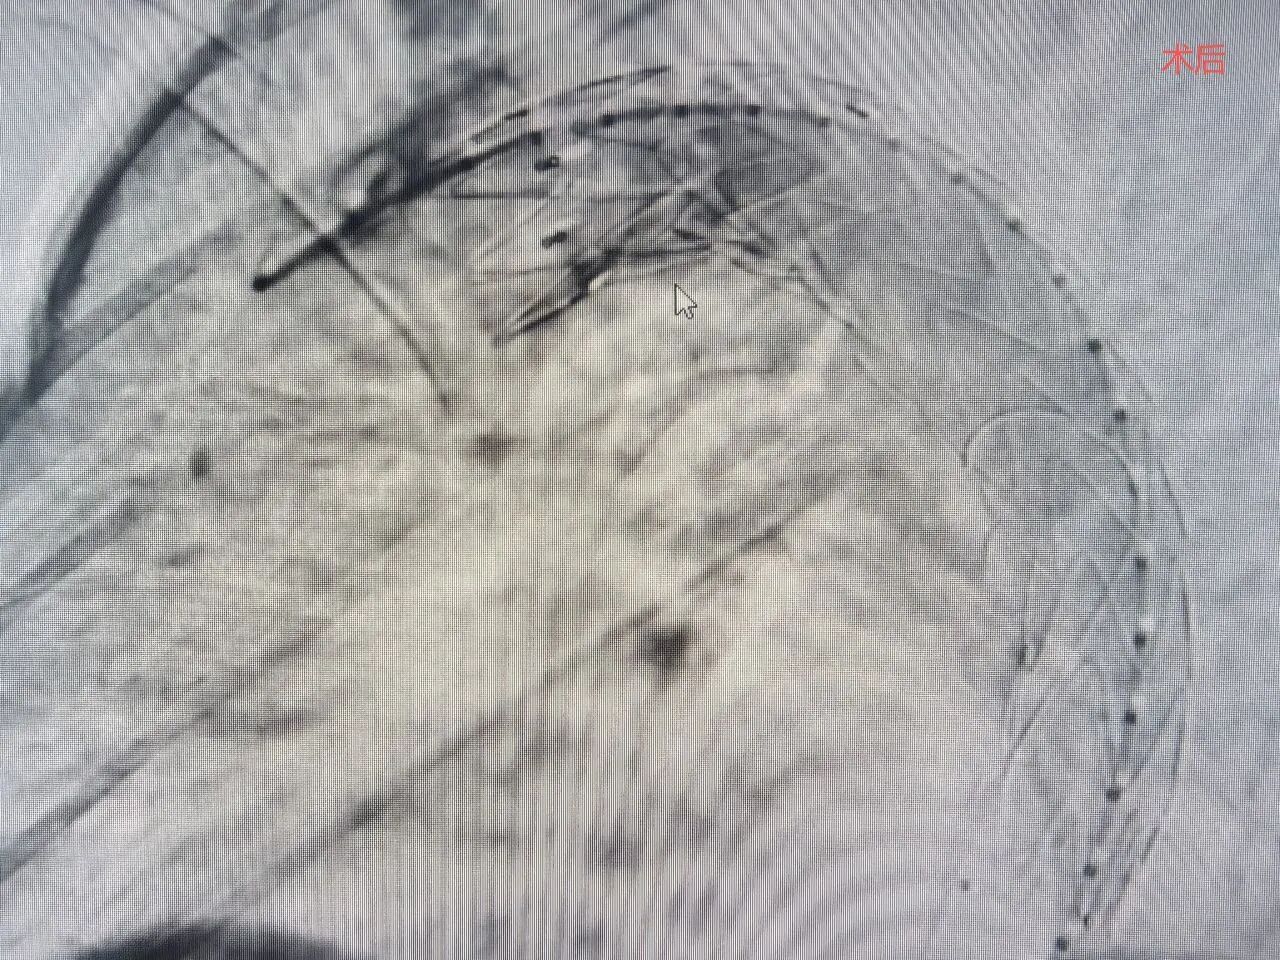

导丝轻柔地通过病变血管,覆膜支架被缓缓推送至主动脉弓降部,定位、释放、贴合——整个过程一气呵成。术后即刻造影显示:支架定位精准,形态良好,破口被完美封堵,真腔血流通畅,假腔消失不见。这颗威胁患者生命的“重磅炸弹”被成功拆除!

目前,患者术后恢复良好,胸痛症状完全消失,已经脱离生命危险,正在康复之中。